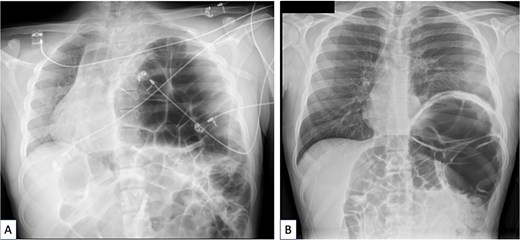

An 18-year-old male originally from Egypt presented to the emergency department with severe abdominal pain suggestive of bowel obstruction. Over the preceding 10 days, he had experienced recurrent non-bilious vomiting, and bowel movements had ceased for 48 h. Since childhood, he had suffered from frequent constipation and had developed chronic abdominal pain during the past year. He had never engaged in sports, particularly endurance activities, and had taken no chronic medication other than laxatives. Physical examination revealed a markedly distended abdomen and absence of breath sounds on the left side. Contrast-enhanced chest and abdominal computed tomography (CT) demonstrated a mesentero-axial sigmoid volvulus with a characteristic “whirl sign,” without evidence of perforation (Fig. 1A and B). The most distended segment of colon had migrated into a large left diaphragmatic eventration, causing mediastinal shift and complete left lung atelectasis (Figs 1C and 2A). Laboratory tests showed no inflammatory response. Under general anesthesia, an initial bedside endoscopic decompression achieved partial detorsion, requiring a second successful endoscopic procedure. Owing to the presence of megacolon and marked mesenteric laxity, the risk ofrecurrence remained high, and surgical management was indicated. Due to organizational constraints, a two-step surgical strategy was adopted. First, an open sigmoidectomy with mechanical end-to-endcolorectal anastomosis was performed. Before thoracic correction, dynamic thoracic magnetic resonance imaging confirmed persistent massive eventration (Fig. 3A), with major mediastinal displacement and absence of contractile activity of the left hemidiaphragm. Pulmonary function tests showed an forced expiratory volume in one second at 71% of predicted (decreasing to 64% in the supine position) and a vital capacity of 74%. Two months later, diaphragm plication reinforced with prosthetic mesh was performed through a video-assisted lower lateral mini-thoracotomy. Intraoperative findings confirmed a massive eventration leaving minimal space for the compressed left lung (Fig. 3B). The diaphragm was extremely thin—~1 to 2 mm—appearing nearly transparent after incision (Fig. 3C). Postoperative recovery was uneventful, except for a transient functional bowel obstruction managed medically. Histopathologic examination of the resected colon ruled out Hirschsprung disease and revealed chronic ischemic changes with fibrosis separating the external muscular layer (Fig. 3D). Four months after the final procedure, the patient showed clear clinical improvement, with normalized bowel habits and the ability to climb several flights of stairs without dyspnea. Chest X-ray confirmed left lung re-expansion and mediastinal repositioning (Fig. 2B). Chronic colonic distension persisted without symptoms and exerted mild upward pressure on the repaired left hemidiaphragm.

(A) Chest X-ray done when acute sigmoid volvulus occurred, revealing the major diaphragmatic eventration causing severe contralateral mediastinal shift and complete left lung atelectasis. (B) Chest X-ray done 4 months after sigmoidectomy and diaphragm plication. The left lung is well reexpanded and the mediastinum is in good position. The left hemidiaphragm is stabilized at a correct but high level because of persistent megacolon despite sigmoidectomy.